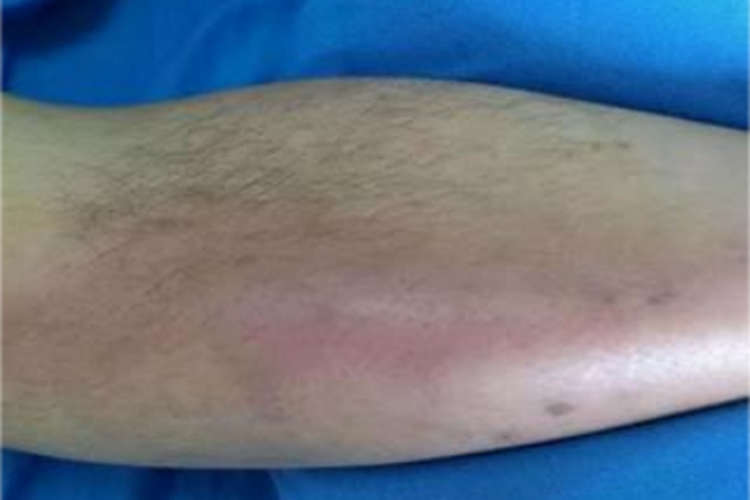

下肢深静脉血栓可表现为小腿皮肤发红肿胀,皮肤紧绷发亮,可伴有下肢疼痛,随着疾病进展,皮肤温度可升高,肿胀范围扩大,蔓延至整个下肢。

下肢深静脉血栓会堵塞深静脉,使静脉内压力增加,血液循环受阻,导致血液堆积在小腿,进而引起局部肿胀。同时,血栓还会激发炎症反应,释放炎细胞因子,引起血管扩张,血管通透性增加,导致红细胞、白细胞和血小板逐渐渗出血管,使小腿皮肤发红。